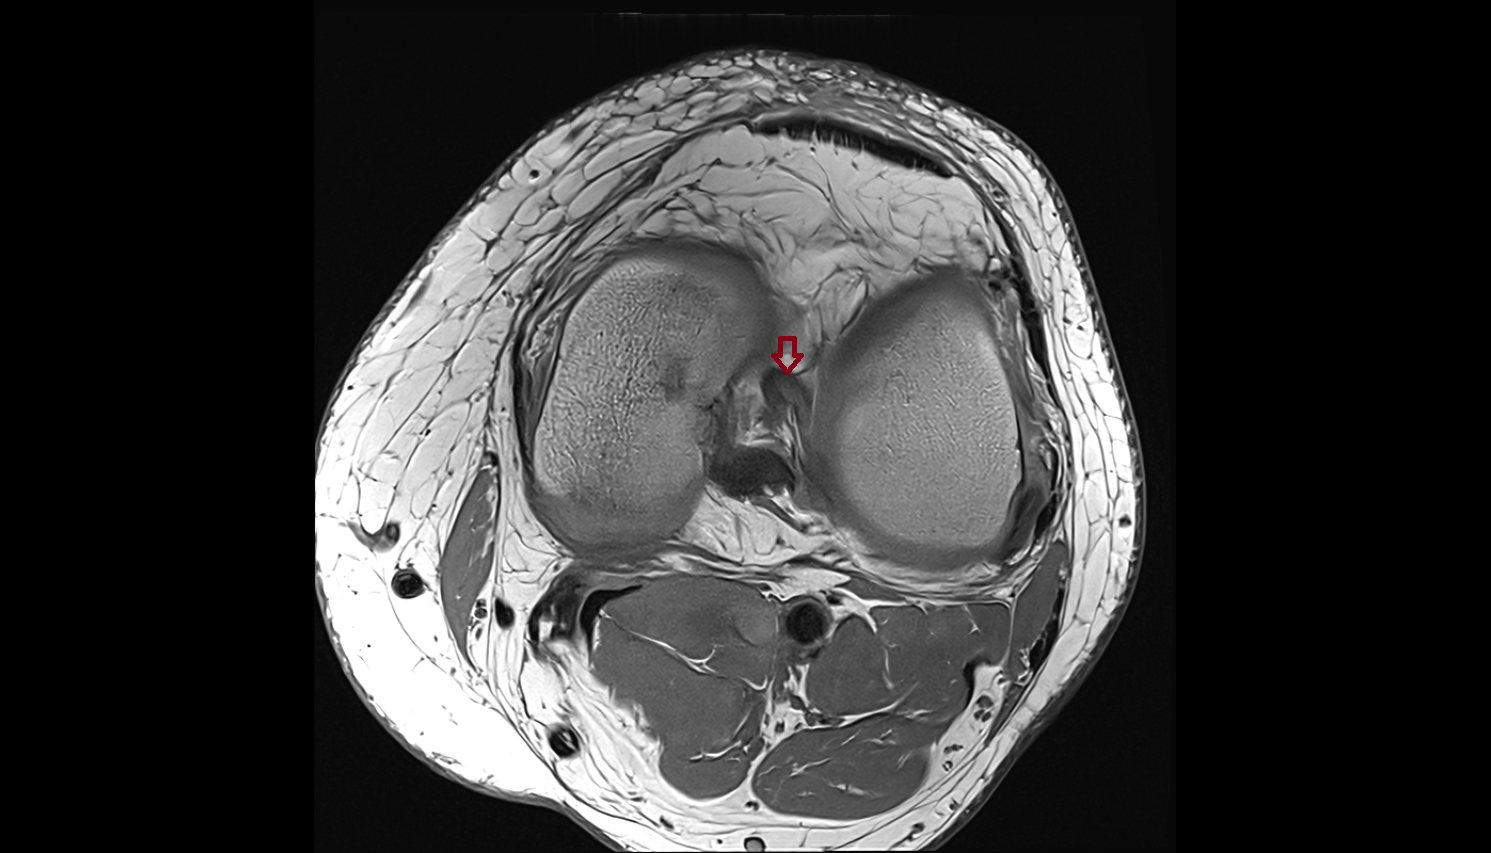

- Anterior cruciate ligament

- Medial meniscus

- Lateral meniscus

- Knee Joint